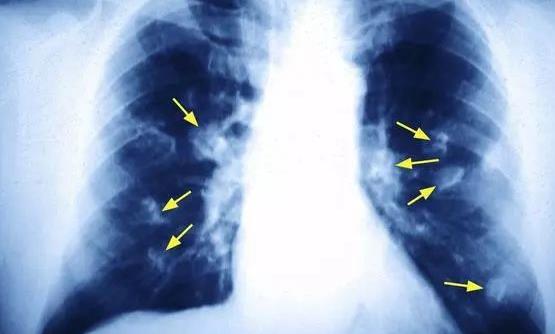

我國(guó)國(guó)家癌癥中心的最新報(bào)告顯示,肺癌是女性第二高發(fā)的癌癥,僅次于乳腺癌。40-50歲女性中肺癌患者人數(shù)已經(jīng)接近男性,達(dá)到了1:1的比例。但是國(guó)內(nèi)女性的吸煙率很低,為何發(fā)生肺癌的概率卻如此“不協(xié)調(diào)”地高呢?下面跟隨360常識(shí)網(wǎng)了解一下吧!

對(duì)肺癌患者長(zhǎng)達(dá)5年的追蹤病因調(diào)查發(fā)現(xiàn),70%的男性肺癌患者死于吸煙病因,只有18%的女性患者因吸煙或長(zhǎng)期被動(dòng)吸煙致肺癌。

在非吸煙女性肺癌危險(xiǎn)因素中,超過60%的女性長(zhǎng)期接觸廚房油煙;有32%的女性燒菜喜歡用高溫油煎炸食物,同時(shí)廚房門窗關(guān)閉,廚房小環(huán)境油煙污染嚴(yán)重;25%的女性家中廚房連著臥室,冬天又很少開窗,高溫油煙久久不散,甚至睡覺時(shí)也在吸油煙!

調(diào)查表明,這種病因在中老年女性肺癌患者中特別突出,危險(xiǎn)因素達(dá)到了正常人的2-3倍。